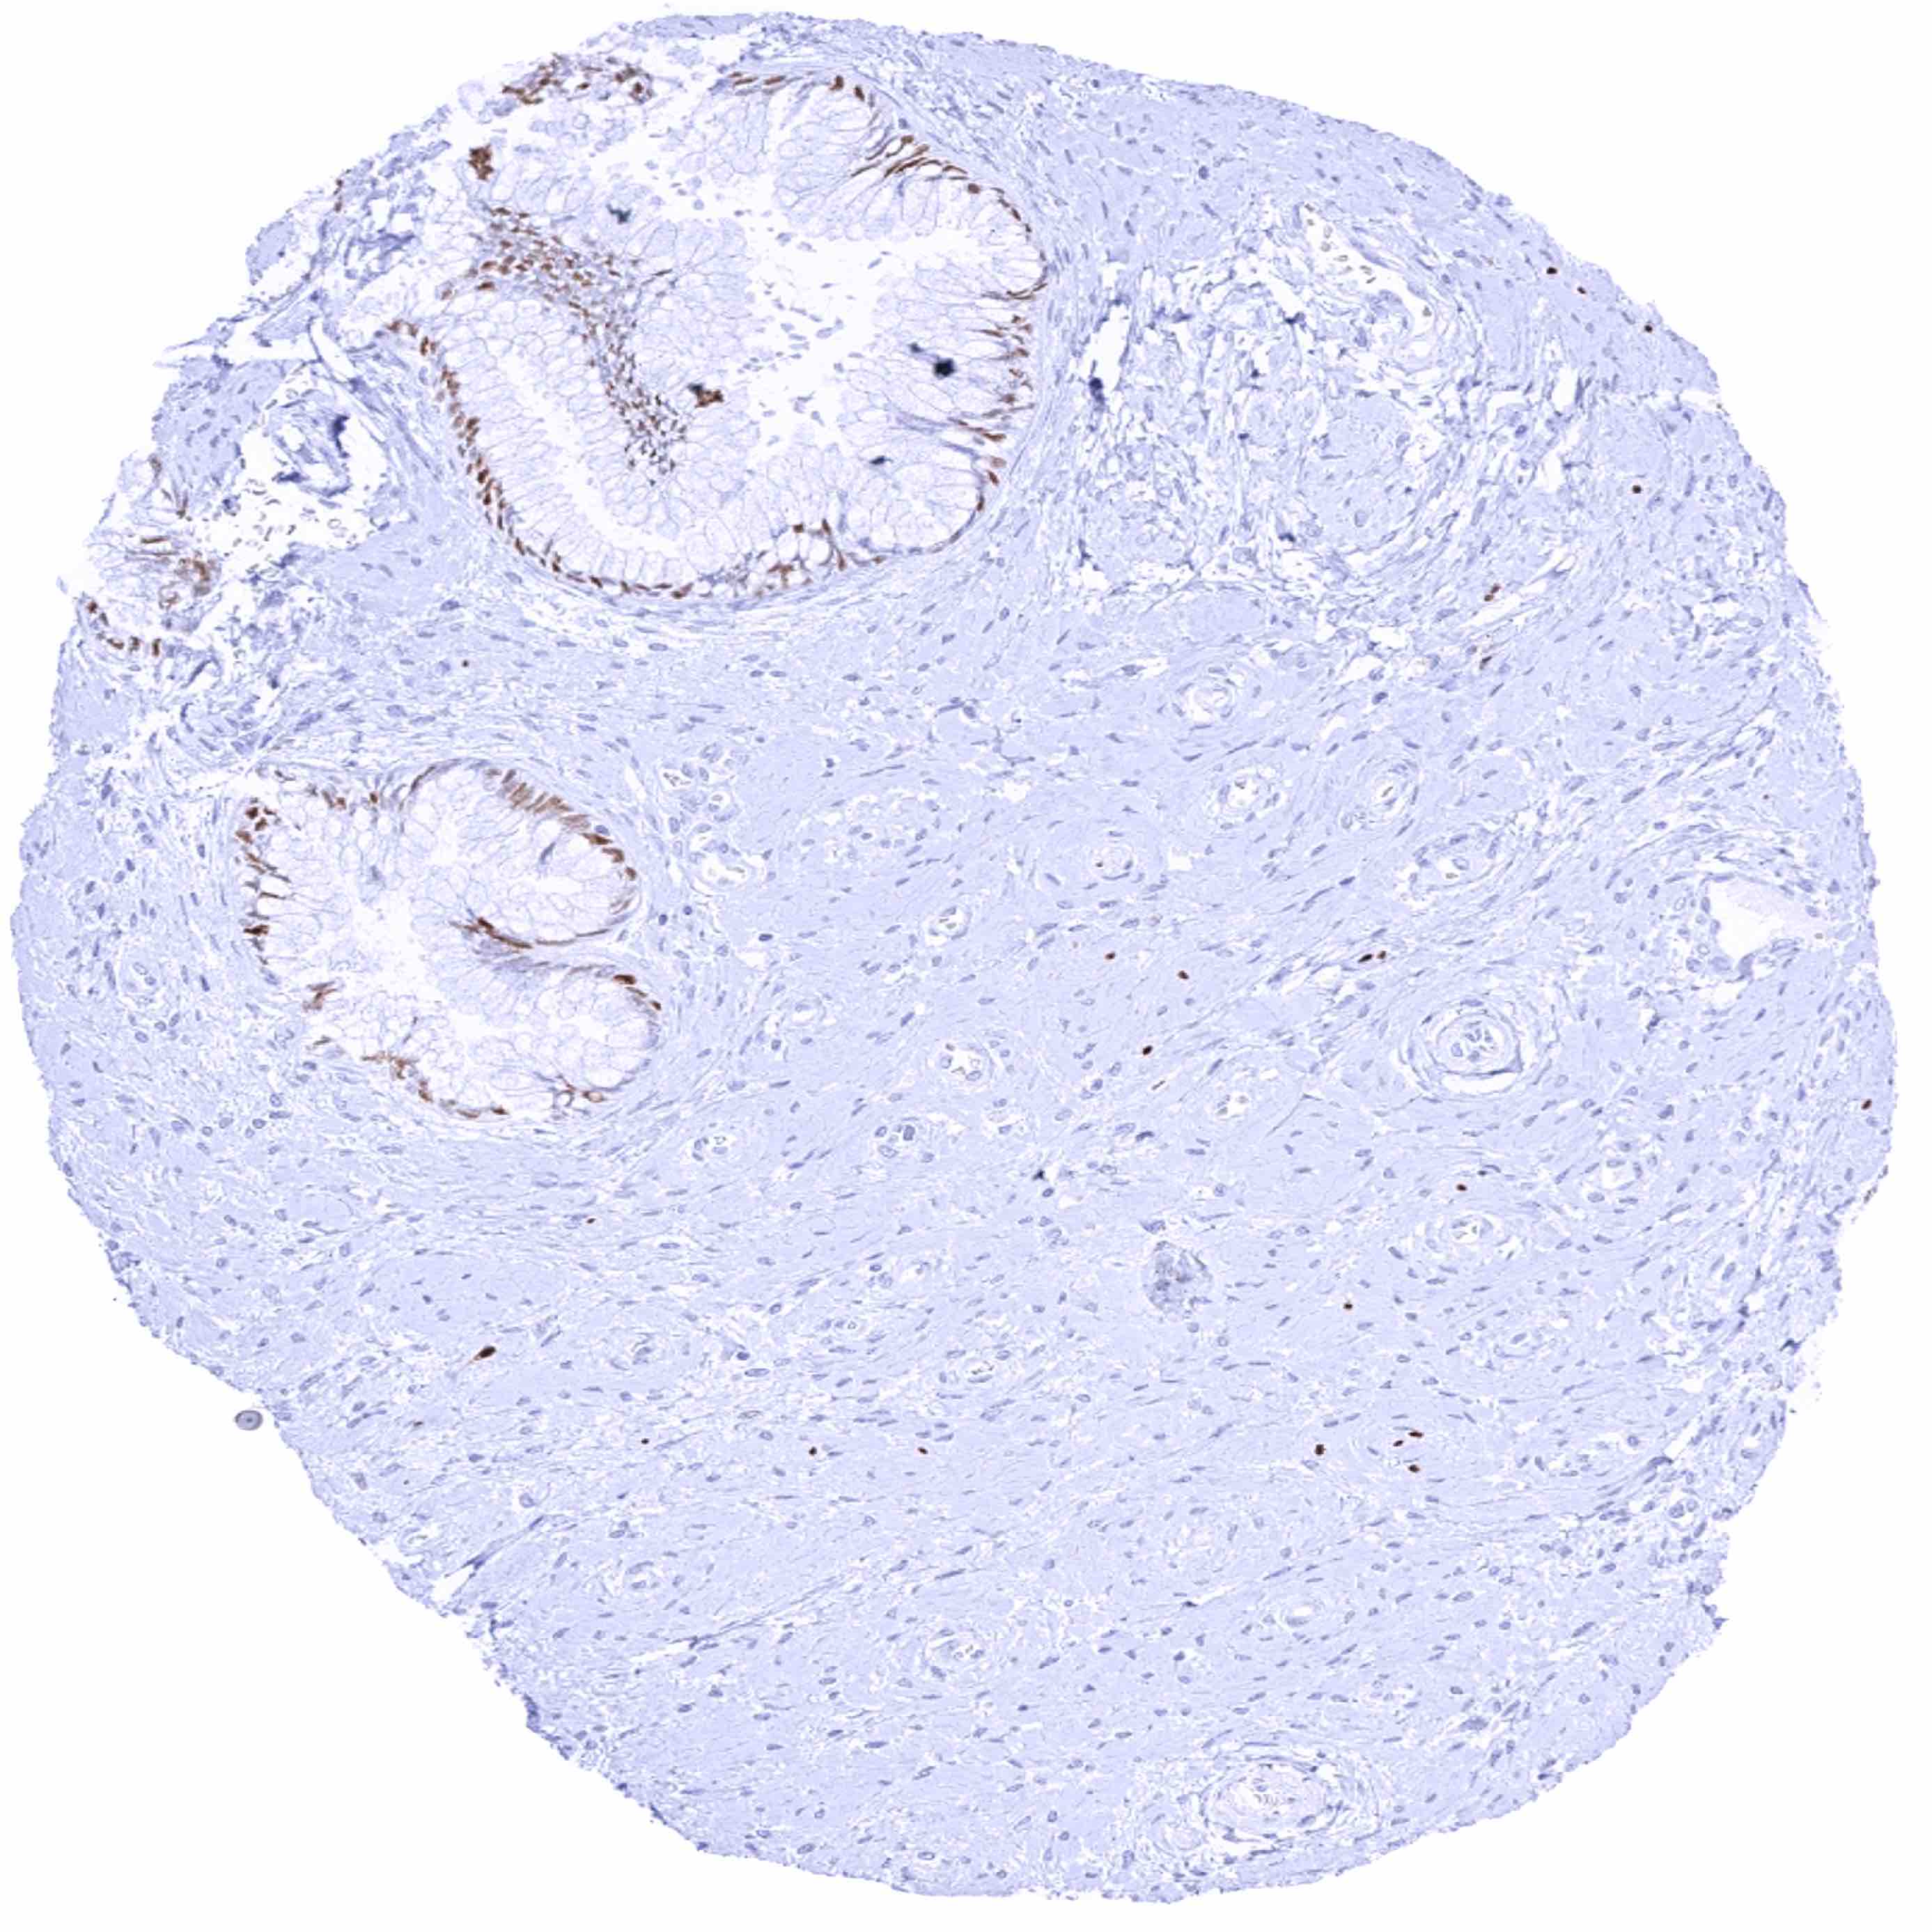

Prostate – Strong SOX2 positivity of a fraction of basal cells